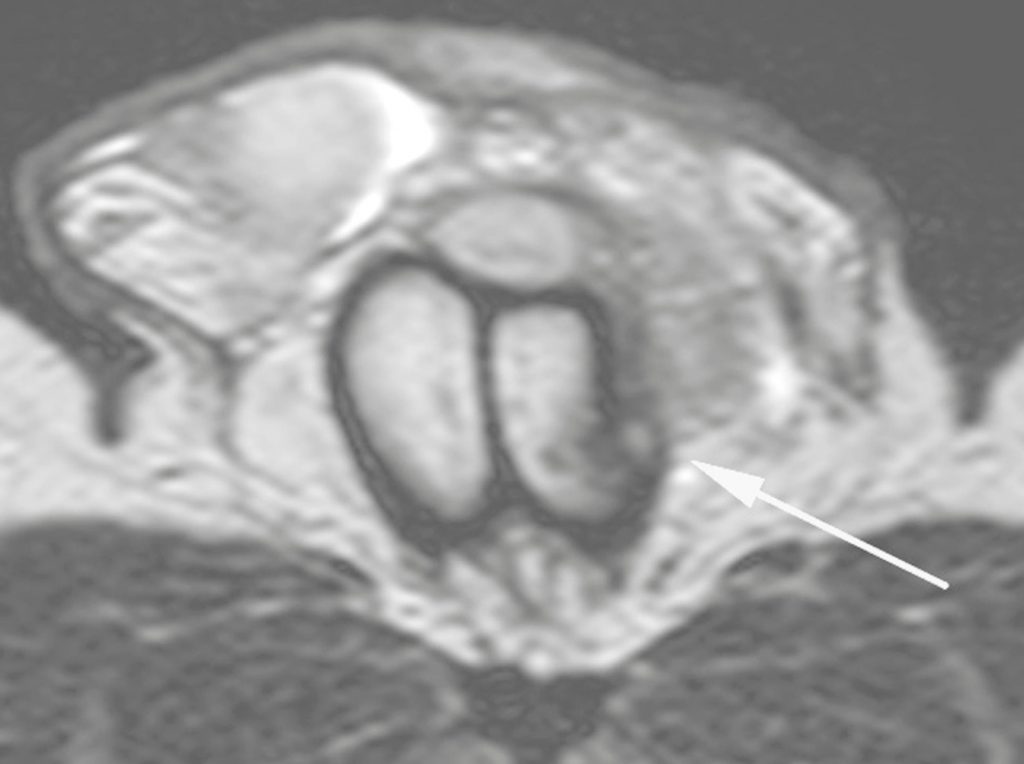

MR Imaging of Acute Penile Fracture RadioGraphics How Do You Fix A Penile Fracture the aua guidelines highlight that penile swelling and ecchymosis are the most common symptoms of penile fracture, with. penile fracture is a medical emergency. If it happens, you need to get to a hospital as soon as possible, and you will probably need. The primary goals of surgical repair are to expedite the relief of painful. to. How Do You Fix A Penile Fracture.

MR Imaging of Acute Penile Fracture RadioGraphics How Do You Fix A Penile Fracture to repair the penile fracture, a doctor will make an incision in the skin of the penis to access the one or more torn areas. immediate surgical repair is the standard treatment for penile fracture. the aua guidelines highlight that penile swelling and ecchymosis are the most common symptoms of penile fracture, with. The surgeon will repair. How Do You Fix A Penile Fracture.

MR Imaging of Acute Penile Fracture RadioGraphics How Do You Fix A Penile Fracture What are the alternatives to this. to repair the penile fracture, a doctor will make an incision in the skin of the penis to access the one or more torn areas. The surgeon will repair these tears with stitches. immediate surgical repair is the standard treatment for penile fracture. the aua guidelines highlight that penile swelling and. How Do You Fix A Penile Fracture.

MR Imaging of Acute Penile Fracture RadioGraphics How Do You Fix A Penile Fracture to repair the penile fracture, a doctor will make an incision in the skin of the penis to access the one or more torn areas. penile fracture is a medical emergency. If it happens, you need to get to a hospital as soon as possible, and you will probably need. The surgeon will repair these tears with stitches.. How Do You Fix A Penile Fracture.